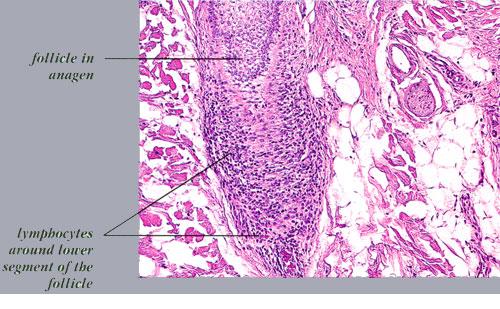

The diagnostic pathologic feature is peribulbar lymphocytic inflammation (“swarm of bees”) affecting anagen follicles or follicles in early catagen. The inflammatory assault on anagen follicles induces a premature conversion to catagen . Consequently, the number of catagen and telogen follicles found may be marked, approaching 100% . Follicles may enter a persistent phase of telogen in which the hair shaft has already been shed, manifested by the telogen germinal unit .As follicles enter catagen, the lymphocytic infiltrate may persist around the epithelial remnant of the receding follicle and also within and surrounding the collapsed follicular sheaths. Telogen hairs show little to no perifollicular inflammation.

Lymphocytes may also be seen sparsely infiltrating the matrix epithelium of anagen follicles, inducing damage to the matrical cells that includes intra- and intercellular edema, cellular necrosis, and microvesicle formation. One of the earliest findings was shown to be a loss of structural integrity of bulbar keratinocytes in the central part of the supramatrical bulb and shrinkage of hair bulbs toward a club shape . As a result of injury to bulbar melanocytes and keratinocytes, pigment casts, which are clumps of melanin pigment, may be found within the dermal papilla, the sheath of miniaturizing or regressing follicles, or the follicular epithelium . Pigment casts